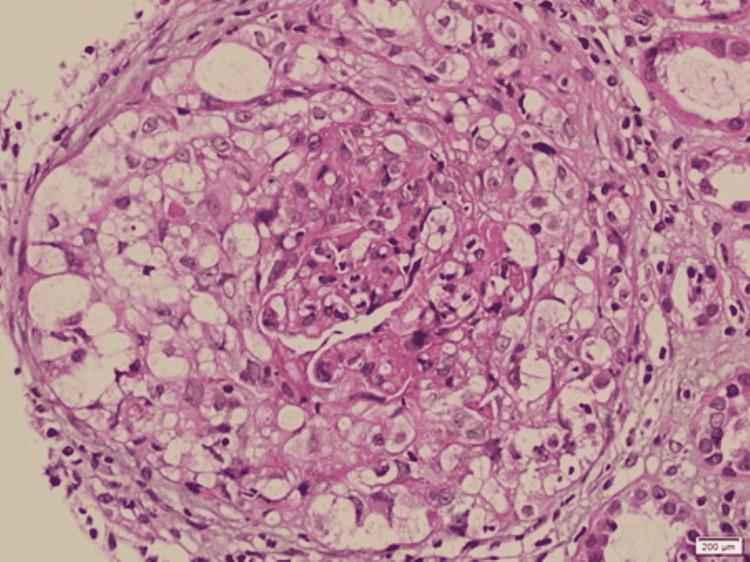

Anti-glomerular basement membrane (anti-GBM) disease is an autoimmune disorder characterized by the production of circulating immunoglobulin G (IgG) antibodies that affect the kidneys and lungs, mainly in the form of rapidly progressive crescentic glomerulonephritis and pulmonary hemorrhage. Typically diagnosed on tissue biopsy, findings mainly include glomerular crescent formation, bright linear staining of GBM for IgG on direct immunofluorescence (IF), and the serologic presence of circulating anti-GBM antibodies. Variation in the laboratory results, where histological findings of linear IgG IF staining were present in the absence of circulating anti-GBM antibodies, have recently led to the use of the term "atypical anti-GBM disease," which usually has a distinct benign clinical outcome as compared to typical anti-GBM disease. We report a case of a middle-aged woman who presented with renal failure without lung involvement. Upon further investigation, the patient was found to have strongly positive serum anti-GBM antibodies, but the tissue biopsy did not show typical findings of the anti-GBM disease. The patient showed modest improvement after multiple sessions of plasmapheresis and steroids, with stabilization of her renal parameters after the initial response. In our case, we will address the possibilities of the discrepancies between the serological and histopathological findings.

抗肾小球基底膜(anti-GBM)病是一种自身免疫性疾病,其特征是产生循环免疫球蛋白G(IgG)抗体,主要以快速进展性新月体性肾小球肾炎和肺出血的形式影响肾脏和肺。通常通过组织活检进行诊断,主要发现包括肾小球新月体形成、直接免疫荧光(IF)下GBM对IgG的明亮线性染色以及循环抗GBM抗体的血清学存在。实验室结果存在差异,即在线性IgG IF染色的组织学发现存在时却没有循环抗GBM抗体,这最近导致了“非典型抗GBM病”这一术语的使用,与典型抗GBM病相比,其通常具有明显不同的良性临床结局。我们报告一例中年女性病例,该患者出现肾衰竭但无肺部受累。进一步检查发现,患者血清抗GBM抗体呈强阳性,但组织活检未显示抗GBM病的典型表现。经过多次血浆置换和类固醇治疗后,患者病情有适度改善,初始反应后肾脏参数稳定。在我们的病例中,我们将探讨血清学和组织病理学结果之间差异的可能性。